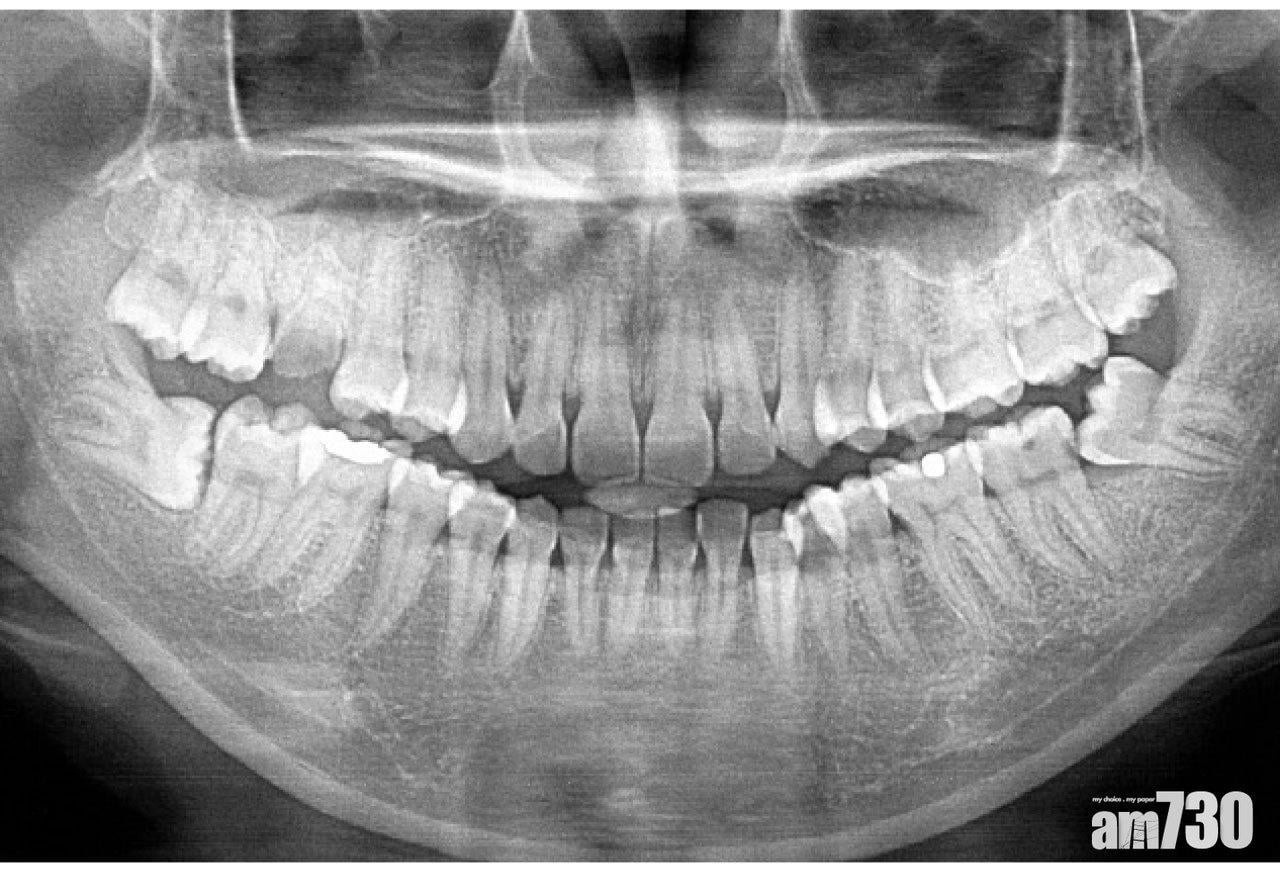

牙齒的琺瑯質和象牙質等成分放射密度高,有效吸收阻擋X光,於是在X光片上呈偏白。相反,口腔內的空氣和軟組織放射密度低,不能阻止X光到達菲林,所以呈偏黑。曾有學生問,他學過初期蛀牙的臨床跡象是牙齒上出現白斑,那麼白斑在X光片上是否也呈現白色呢?

了解X光菲林背後的物理和化學,就能消除這個疑惑了。初期蛀牙引致的牙齒內部礦物質流失,會改變其光學性質,造成肉眼所見的白斑。礦物質流失亦會降低其放射密度,造成蛀牙部分於X光片上偏黑,較接近空氣和軟組織的顏色。我曾大惑不解:金屬牙冠和種植體擋住了所有X光,影出來白色。那為甚麼一張新的、沒有接觸過X光的菲林沖出來,是透明而非白色的呢?行內的權威李醫生,說答案顯而易見:既然兩者本質一致,表象自當然一樣,所謂的白色,其實是透明 。我將圍繞住白色的黑色剪走,剩下的白色部分和透明X光片湊到一塊。兩者果然一模一樣!我的思想頓時變得澄明。課本沒刻意提及,是認為學生自己會想得通吧。